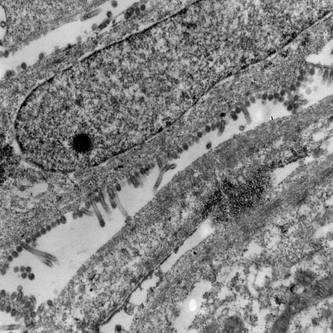

高病原性鳥インフルエンザウイルスの電子顕微鏡写真です。

2. 2005年6月26日の茨城県の発生例から分離された株(H5N2)

| SPF鶏(健康な鶏)からとった細胞を培養して、その細胞にIbaraki/1/05株(H5N2)ウイルスを接種したもので、写真は細胞内で増殖したウイルスが細胞表面から飛び出してきている(出芽)像。 *右の写真は左の写真の一部を拡大したもの。細胞の突起からウイルスが出芽している様子がわかります。 SPF: Specific Pathogen Free(特定病原体不在) |